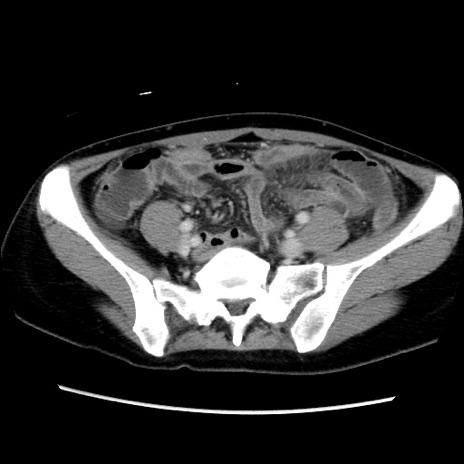

症例39(横断像)

【症例】40歳代女性

【主訴】上下腹部痛

【現病歴】2日目から下腹部痛あり。夜間は痛みで眠れなかった。昨日より上腹部痛と下痢が出現。臥位で痛みは軽快したため、休んでいた。本日になって臥位でも立位でも痛みが強くなってきたため救急要請。

【既往歴】子宮内膜症

【身体所見】部:平坦・軟、左上下腹部に圧痛あり、反跳痛あり。

【データ】WBC 21800、CRP 26.78